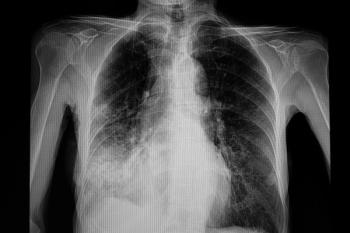

A systematic review reveals declining pediatric pneumococcal complicated pneumonia rates following the introduction of pneumococcal conjugate vaccine 13.

Invasive pneumococcal disease trends have fluctuated greatly over the past 2 decades, with older adults remaining at the center of disease burden.